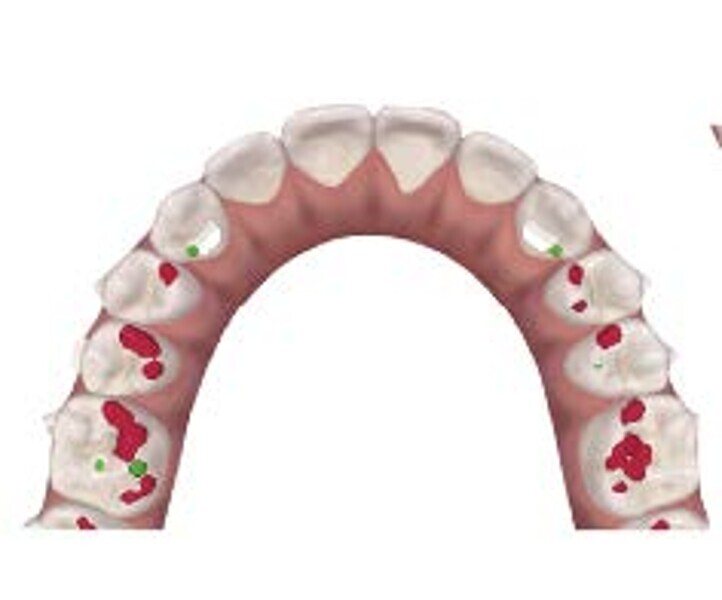

To properly correct deep bite malocclusion with aligners, the Invisalign system (Align Technology) has introduced precision bite ramps, anterior customised bite turbos, embedded into the aligners, and these are available for the lingual surface of the maxillary central and lateral incisors or of the maxillary canines. This feature does not require composite filling like for traditional attachments; it is a lingual extension of the aligner (maximum palatal extension of 3 mm) that creates premature anterior contacts and posterior disocclusion. The ramps are planned to move, stage by stage, in a more occlusal direction, creating the necessary posterior occlusal space to permit lateral and posterior teeth to extrude relatively. The ramps need to be combined with two other features: extrusion attachments on lateral teeth and mandibular incisor pressure areas, a lingual pressure point designed to exert intrusive forces following the long axis of the incisors more effectively. In this way, the levelling of the mandibular curve of Spee will be more reliable, combining two reciprocal movements in two different parts of the arch, anterior intrusion, and posterior extrusion, as indicated in the literature (Figs. 1–8).6, 7

When planning the digital set-up (ClinCheck software), careful levelling of the curve of Spee in 3D needs to be addressed, in particular:

On the vertical plane, the mandibular second molars represent a reference point, so they do not need to be extruded, whereas extrusion should be planned for the first molars, second premolars and (sometimes) first premolars (depending on the severity of the curve). The intrusion should be achieved simultaneously from canine to canine, creating a normal overbite.8

On the sagittal plane, distal tipping of the second and first molars will support the curve of Spee levelling, in combination with reciprocal mesial tipping of premolars and canines. This movement is synergic, and distal tipping will favourably partially extrude the molars.

On the transverse plane, the uprighting of premolars and molars reaching a torque close to 0° will create a relative extrusion of the lateral segments, contributing to the levelling of the curve of Spee and premature posterior occlusal contacts.9

The digital treatment plan (ClinCheck) provided 12 aligners for the maxillary arch and 17 for the mandibular arch. The treatment objectives were focused on coupled vertical movements of posterior extrusion and anterior intrusion by means of bite ramps, providing for posterior disocclusion and anterior intrusion of mandibular teeth by means of extrusion attachments needed for mandibular arch levelling. The maxillary and mandibular incisors were proclined to level the upper and lower curve of Spee and to support the flat profile and the lips. Class II elastics were planned to support mandibular proclination and heavy posterior occlusal contacts with relative posterior extrusion. Lateral and posterior maxillary torque were planned to be close to 0°, to achieve wider arch design and ideal intercuspation. No digital over-engineering was planned in the set-up. Because of the age of the patient, the aligners were changed every ten days for a treatment time of less than six months. At the end of the first stage of aligners (Figs. 20–24), an additional stage was planned to improve molar intercuspation without elastics with a digital plan of five further aligners. This brought the total treatment time to 7.5 months since the additional aligners were changed every week.